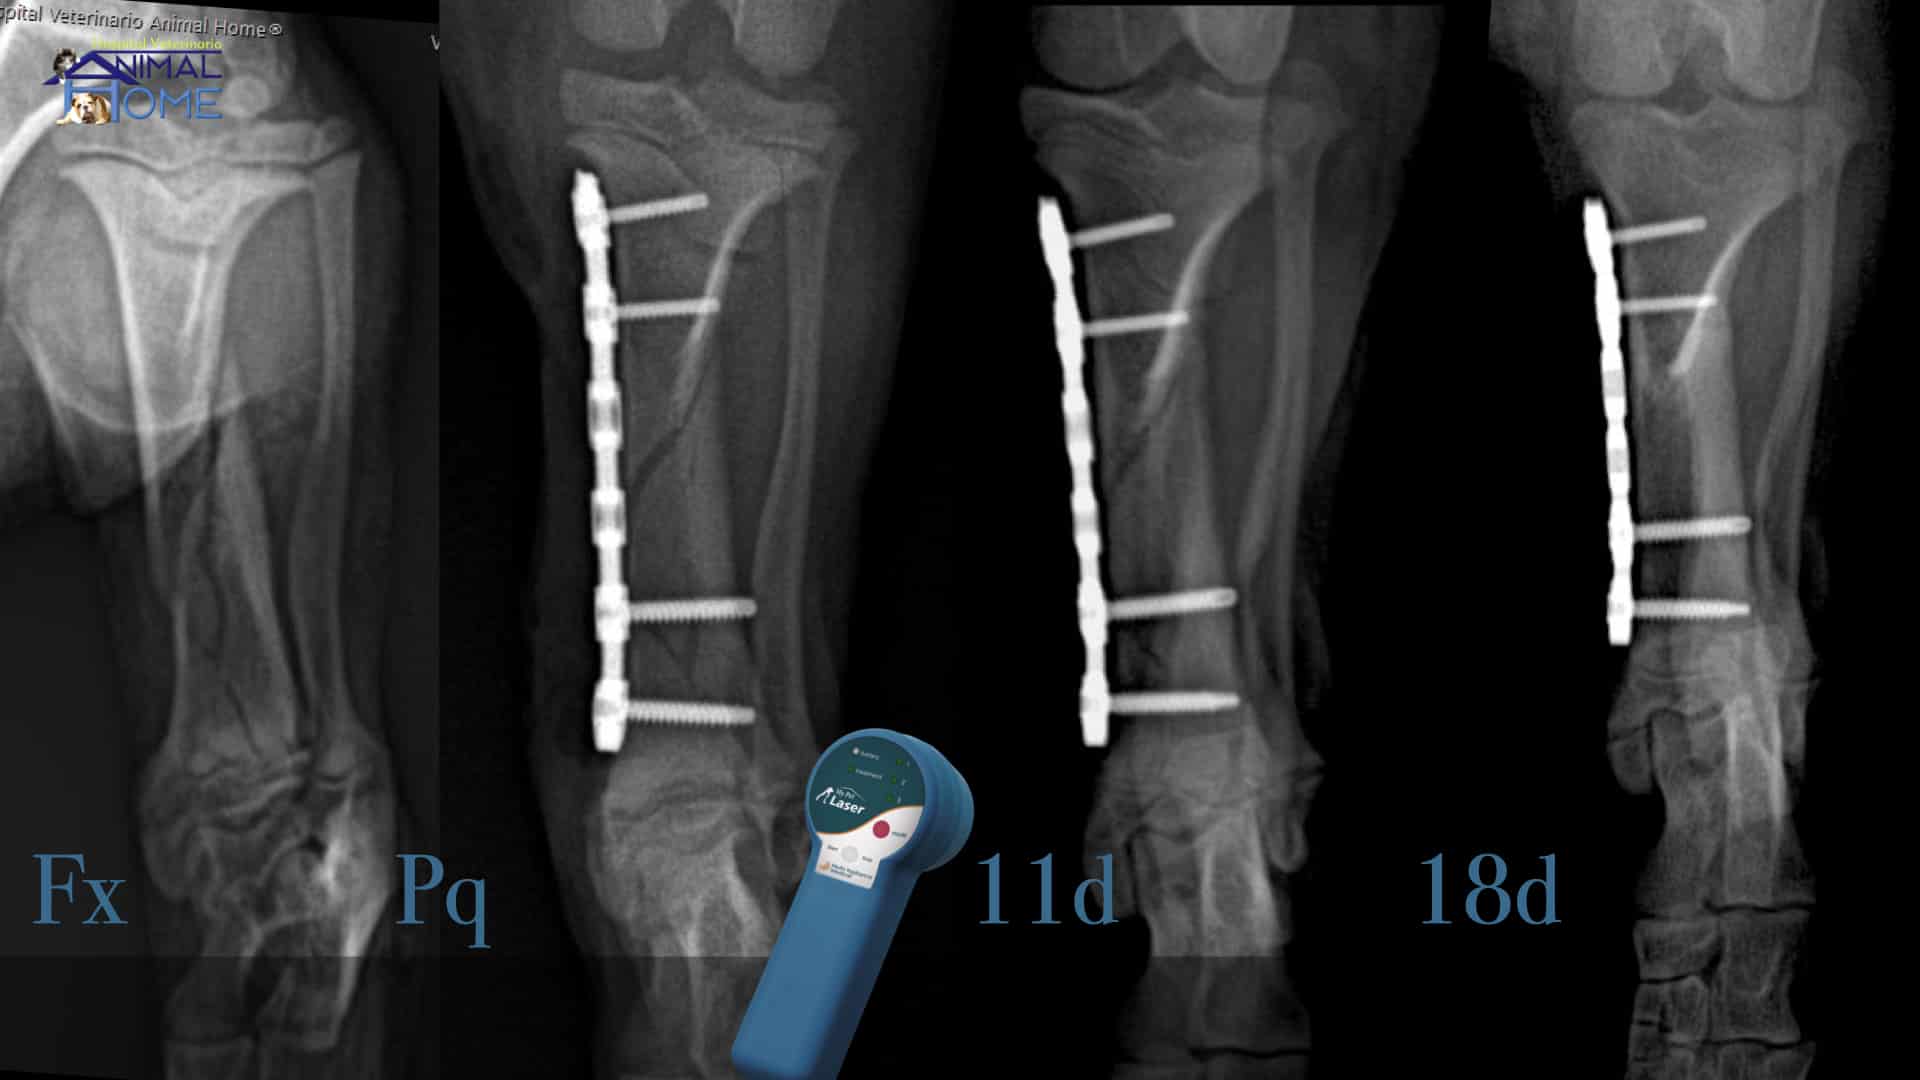

- Fracturas óseas